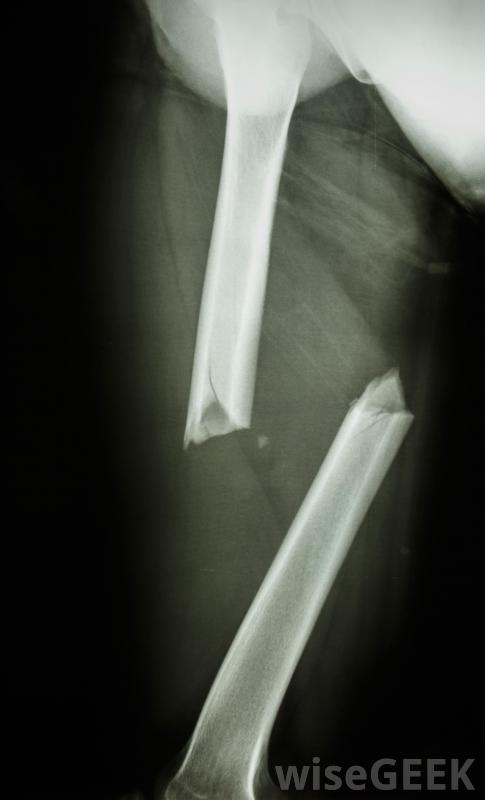

X光片将显示骨骼骨折的严重程度。

撞击性骨折,当一块骨头碎裂,碎片被打入其他骨块,可能是相当严重的,一旦确定损伤程度,应迅速治疗,以避免进一步的问题。如果损伤不太严重,石膏、夹板或吊索可能足以将受伤的骨头固定在适当的位置,以便愈合是的。更大范围的骨折...

撞击性骨折,当一块骨头碎裂,碎片被打入其他骨块,可能是相当严重的,一旦确定损伤程度,应迅速治疗,以避免进一步的问题。如果损伤不太严重,石膏、夹板或吊索可能足以将受伤的骨头固定在适当的位置,以便愈合是的。更大范围的骨折伴有多个骨碎片,可能需要手术将其复位,可能需要螺钉或销钉之类的硬件将其固定。由于此类骨折通常非常痛苦,在愈合过程中可能需要药物来控制它。